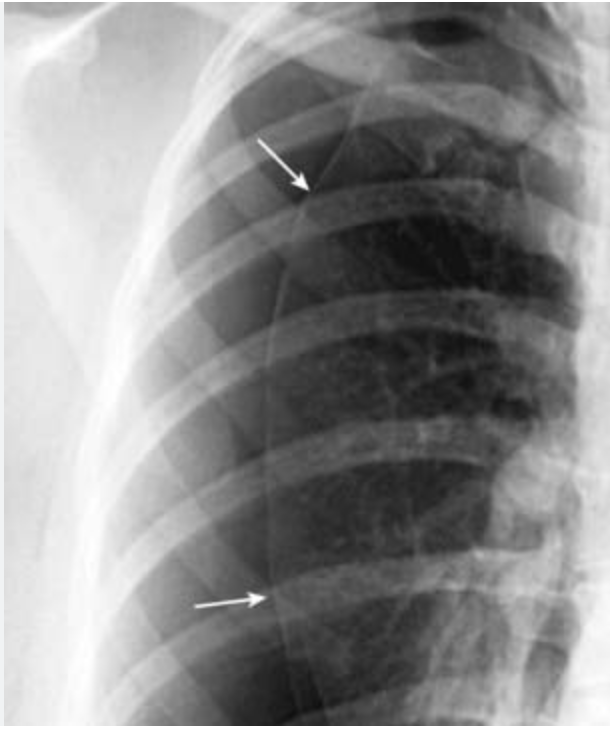

Chest X-ray showing absent lung markings and a visible pleural line.

Mediastinal shift and tracheal deviation away from the affected lung.

An upright posteroanterior chest x-ray has high sensitivity for detecting pneumothorax; it is the initial test of choice when there is suspicion for pneumothorax in the nonacute setting (low risk of tension physiology). However, in the acute setting, where rapid decompensation from tension pneumothorax is possible, upright chest x-ray is not appropriate. In addition, posteroanterior chest x-ray requires standing, which may not be possible in some patients (e.g. with pelvic fracture). Additionally, expiratory chest x-rays do not provide additional sensitivity compared to inspiratory chest x-rays; therefore, inspiratory chest x-rays are generally used when evaluating for pneumothorax. A portable supine anteroposterior chest x-ray can be quickly obtained in the acute setting; however, the sensitivity for detecting pneumothorax is estimated at ~50%, far below that for bedside ultrasonography. It is an acceptable alternative when relatively rapid confirmation of pneumothorax is needed and bedside ultrasonography is unavailable.